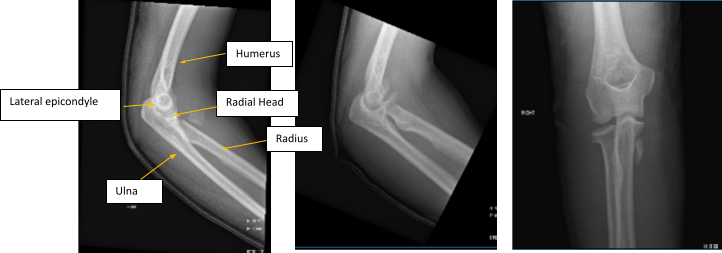

Figure 1. AP Oblique and Flexion Lateral Projection of Right Elbow

Hemarthrosis and a comminuted, affected, acute radial head fracture is present. The plantar-medial portion of the proximal shaft of the right ulna is home to a fracture fragment that has been severely misaligned. Though no donor defect is visible, this could be a fragment of the radial head that has been significantly displaced. A second fracture site is also a possibility.